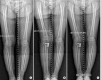

Purpose: To compare the radiographic and clinical results of medial open wedge high tibial osteotomy (OWHTO) using autogenous bone graft and allogenous cancellous bone graft for medial compartment osteoarthritis of the knee with two-year follow-up.

Materials and methods: Fifty-one patients (52 knees) who underwent medial OWHTO from October 2007 to April. 2010 were included in the study. The patients were divided into group I (n=29) that received an autogenous tricortical bone graft and group II (n=23) that received an allogenous cancellous bone chip graft. The radiographic parameters (preoperative anatomical and mechanical femorotibial angles, modified tibial bone varus angle, and posterior tibial slope), clinical parameters, bone union period, and complications were evaluated from medical records.

Results: The radiographic and clinical outcomes did not show significant difference between two groups. The average bone union period was 11.7 weeks in group I and 12.1 weeks in group II. The visual analog scale score on the first postoperative day was significantly higher in group I than group II.

Conclusions: Medial OWHTO using allogenous cancellous bone graft for medial compartment osteoarthritis of the knee can be considered as an alternative treatment method that provides equivalent radiographic and clinical results of OWHTO using autogenous bone graft and causes less immediate postoperative pain.